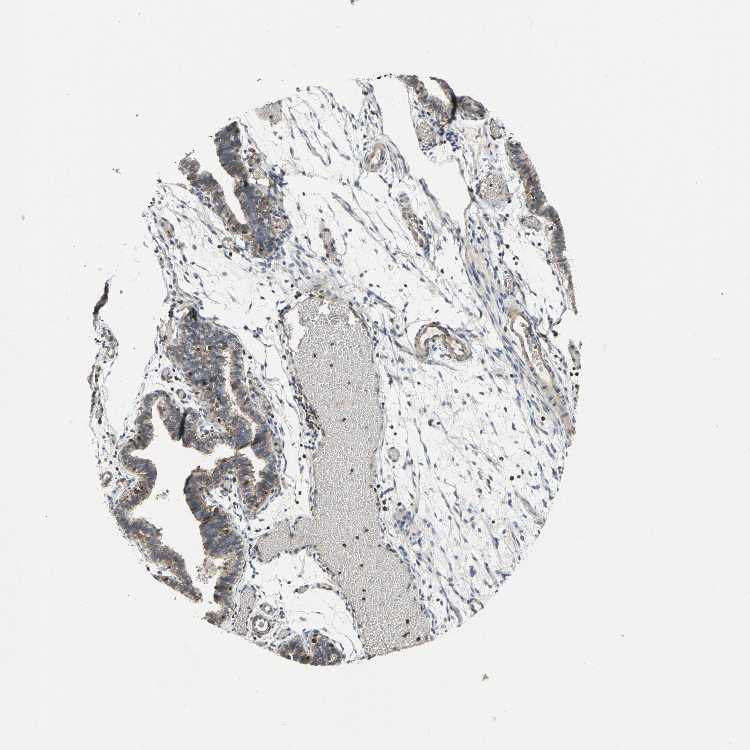

FALLOPIAN TUBE - Antibody stainingi

Antibody staining in the annotated cell types in the current human tissue is reported as not detected, low, medium, or high, based on conventional immunohistochemistry profiling in selected tissues. This score is based on the combination of the staining intensity and fraction of stained cells.

Each image is clickable and will lead to virtual microscopy that enables deeper exploration of all samples and also displays staining intensity scores, fraction scores and subcellular localization as well as patient and tissue information for each sample.

Antibody HPA029722Antibody HPA029723Antibody CAB005072

Ciliated cells (cell body) Not detected--

Ciliated cells (cilia axoneme) Not detected--

Ciliated cells (ciliary rootlets) Medium--

Ciliated cells (tip of cilia) Medium--

Glandular cells -LowMedium

Non-ciliated cells Medium--